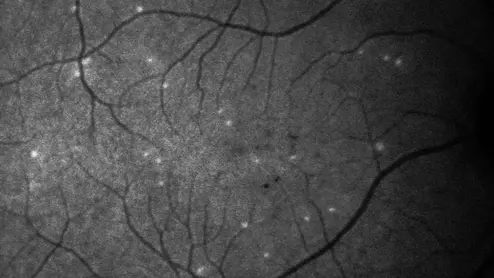

retina test DARC

The test may also have a second important use—improving the treatment of COVID-19 patients.